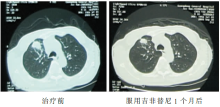

2009-09-02 胸部CT示右肺上叶肿块,大小约29×25 mm,纵隔内气管前、隆突下、肺门淋巴结肿大,最大者约21×28 mm,考虑为右上肺周围型肺癌并肺门纵隔淋巴结转移可能性大,见 图1和 图2。

2009-10-07胸部CT示右上肺肿物及肺门纵隔淋巴结较前明显缩小。